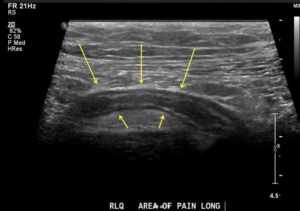

Острое воспаление придатка слепой кишки – аппендикса. Самая распространенная патология брюшной полости, 90% случаев подобных симптомов приходится на аппендицит.

Характерные симптомы:

- боль появляется в околопупочной области, переходит в правый бок, беспокоит постоянно, усиливается, если человек покашливает или смеется, уменьшается, когда больной лежит на правом боку,

- тошнота и рвота,

- задержка стула или понос,

- может незначительно повыситься температура.

У детей – высокая температура, диарея и многократная рвота, они становятся капризными и вялыми. У пожилых пациентов симптомы стертые: дискомфорт незначительный, температура не повышается. Слабо выражены и у беременных. Лечение – хирургическое удаление червеобразного отростка. Это простая операция, через месяц больной возвращается к стандартным будням.